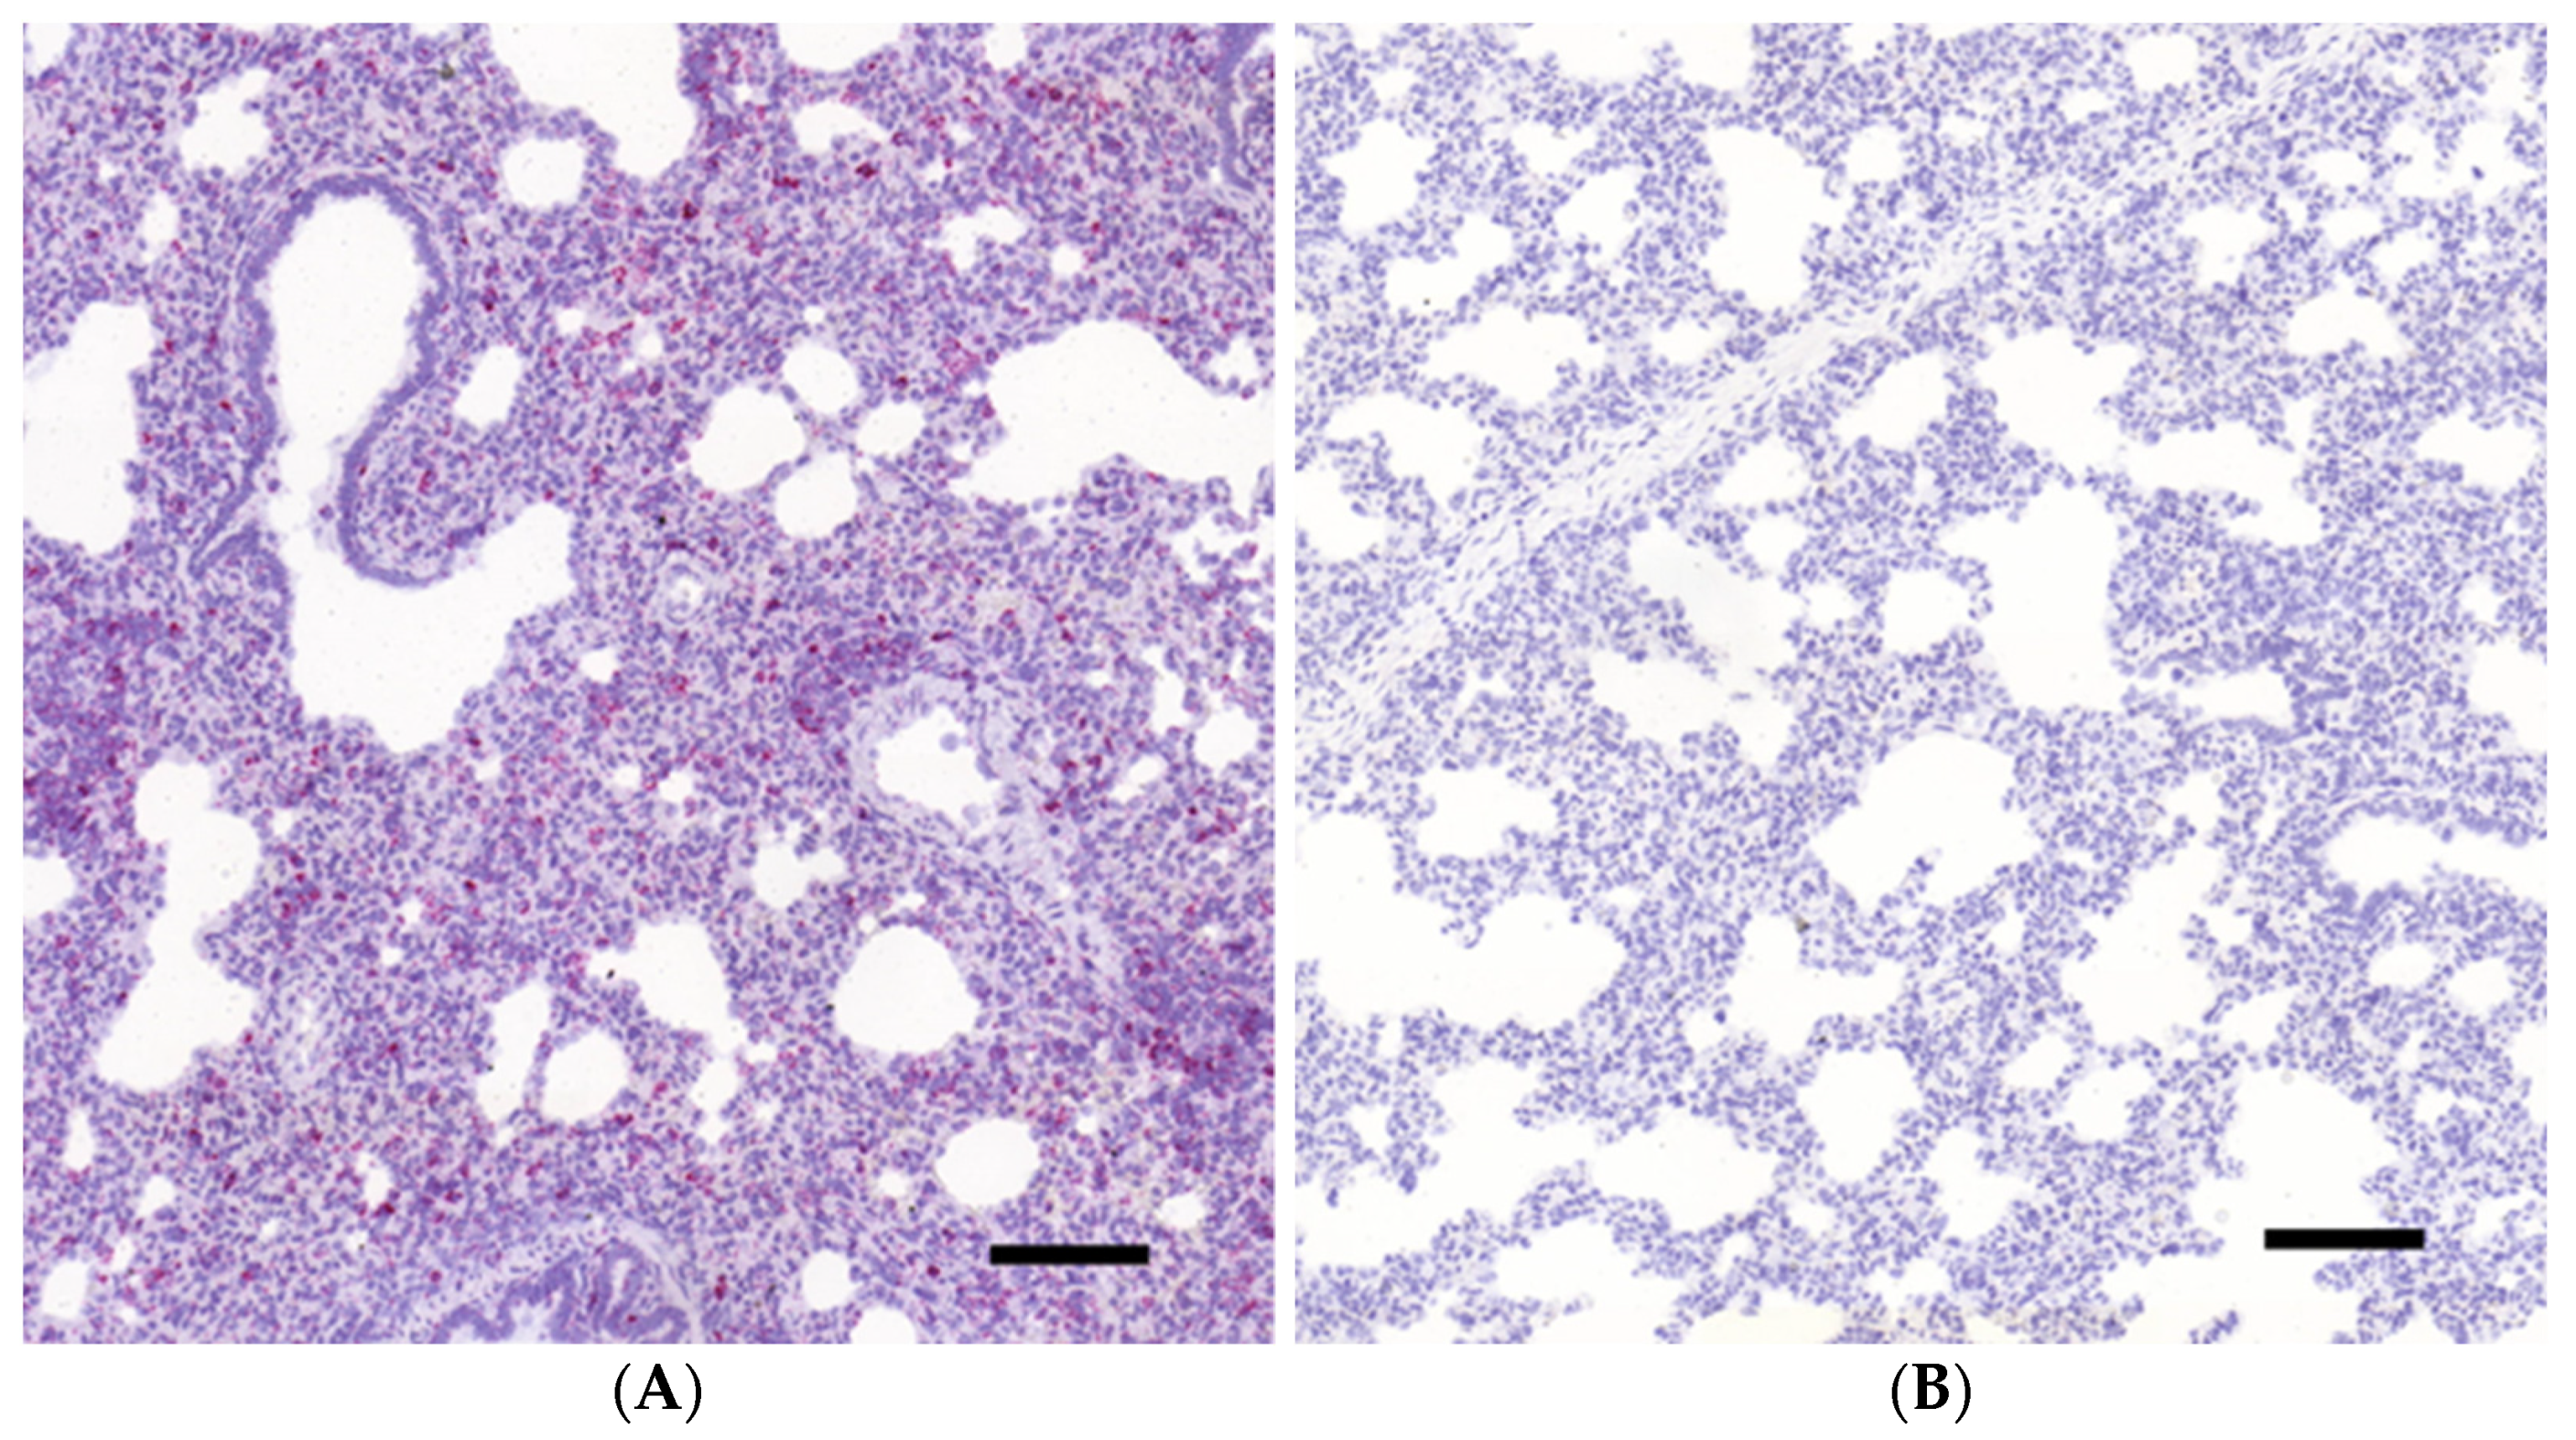

3.1. Histopathology and In Situ Hybridization